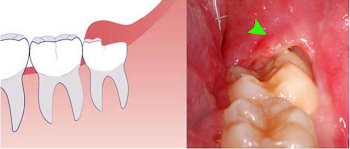

Người khỏe mạnh cắt lợi trùm có nguy hiểm không?

Cắt lợi trùm có nguy hiểm không? Tất cả mọi người trong đời hầu như đều có một lần trải qua viêm lợi trùm. Tuy nhiên, rất ít người hiểu rõ...